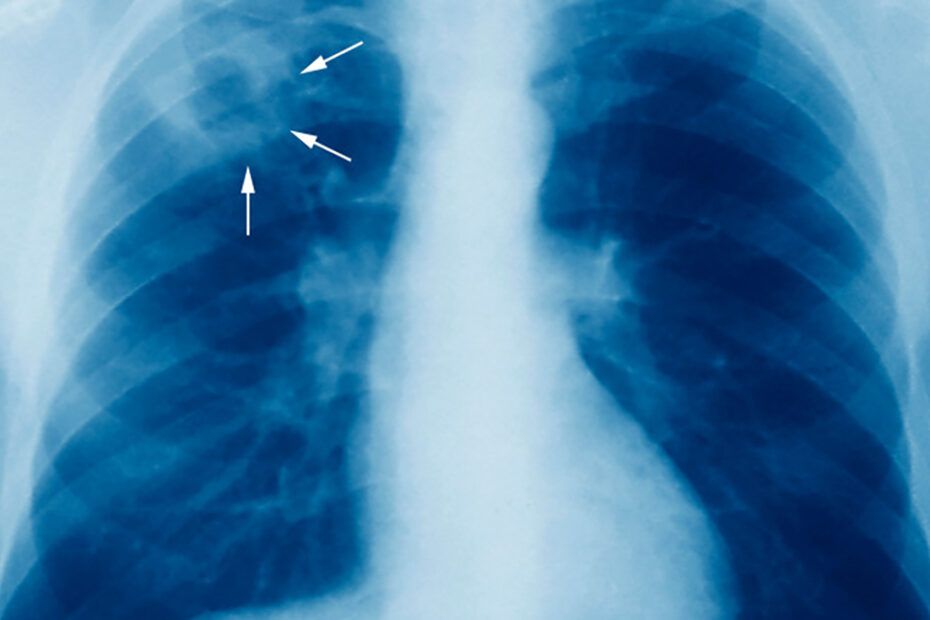

România are cea mai mare povară a tuberculozei din Uniunea Europeană, aproape un sfert (23,4%) din toți pacienții raportați în regiune în 2017.

Institutul Marius Nasta din București a fost dotat cu un echipament de ultimă generaţie, care permite depistarea tuberculozei în doar două ore.

Au fost donate două echipamente GeneXpert cu 10 culori, unul pentru Institutul de Pneumoftiziologie Marius Nasta şi unul care va fi trimis în judeţul Giurgiu. Aceste echipamente sunt cele mai moderne aparate de diagnostic genetic rapid al tuberculozei, care permit detectarea tuberculozei rezistente la antibiotice de tipul rifampicină, izoniazidă, fluorochinolone, etionamidă, amikacină, kanamicină şi capreomicină, în mai puţin de două ore.

„Această tehnologie oferă informații și ne ajută să ajungem la diagnosticul rapid al rezistenței, la principalele antibiotice utilizate în tratamentul tuberculozei, nu doar a tuberculozei sensibile, ci în principal a tuberculozei rezistente, pentru că această metodă scurtează foarte mult timpul de diagnostic, până la momentul la care pacientul poate să beneficieze de o schemă de tratament individualizată.

Un aparat similar, parte a aceleiaşi donaţii, va fi trimis în judeţul Giurgiu. Tuberculoza multirezistentă la medicamente este o ameninţare semnificativă pentru sănătatea publică, în întreaga lume.